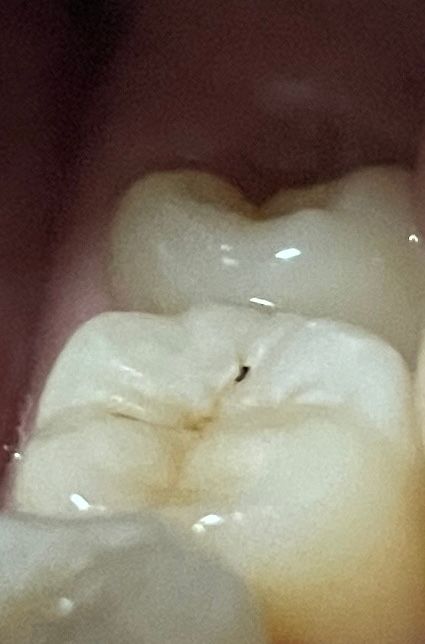

어금니에 검은 게 보이는데 충치 생긴 걸까요?

양치하다가 안쪽에 있어서 몰랐던 건지 아니면 오늘 생긴 건지 못보던 표면에 검은 걸 발견했어요.. 통증은 전혀 없는데 빨리 검진 받아보러 가는 게 낫겠죠?

충치 맞습니다. 검은 점 외에 선상으로 검게 보이는 것이 어느 정도 진행된 것으로 보입니다. 가능한 빨리 치과에 가서 치료해야 합니다.

충치일 가능성이 큽니다. 다만 그 범위가 크지 않아 아직까지 통증은 없을 것으로 보이며 충치가 맞다면 해당 부위를 빨리 제거해주시는 것을 권해드립니다. 치과 방문을 권합니다.

사진에서 보이는 점은 충치인거 같습니다. 치과에 가셔서 검진후 진행되는 충치라면 치료를 받으시는게 좋을것같습니다.